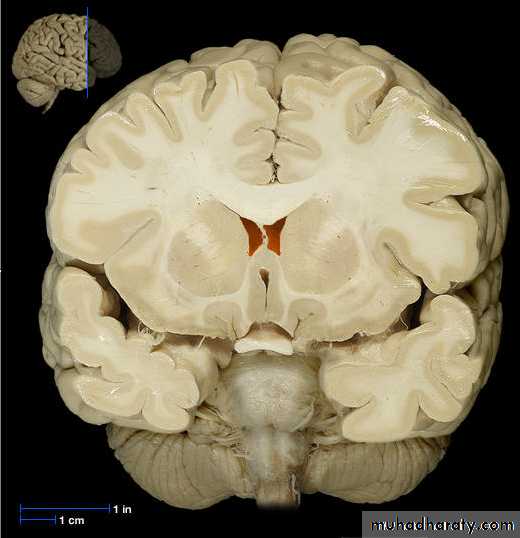

The Choroid Plexus

• The choroid plexus also helps to cleanse the• CSF by removing waste products and other

• unnecessary solutes

• Once produced CSF moves freely through the

• ventricles

Choroid Plexus

• Choroid plexushang from the

roof of each

ventricle

• These plexuses

• form CSF

• The plexuses are

• clusters of thin

• walled capillaries

• enclosed by a

• layer of

ependymal cells

The lateral ventricles

• Situated in the cerebral hemispheres, it has a• body, an anterior horn in the frontal pole, posterior

• horn in the occipital pole & inferior horn in the

• temporal pole.

• The two lateral ventricles are interconnected by

• interventricular foramen and it also communicates

• with the 3rd ventricle.

• All ventricles are lined by ependyma.

3rd Ventricle

• It lies below the lateral ventricles.

• It is a cavity of the diencephalon. In the roof there is

choroid plexus, that produce CSF.

• Superiorly it communicates with the two lateral

ventricles through the interventricular foramen.

• Inferiorly it communicates with the 4th ventricle

through the cerebral aqueduct.

• The lateral wall is formed by thalamus and

• hypothalamus.